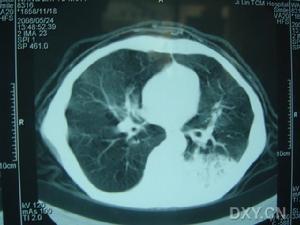

5.急性感染性疾病如敗血症、重症肺炎及傷寒等;

1.機械性腸梗阻 近端腸管內的氣體及液體重吸收和排出受到障礙腸管內細菌因腸內環境的改變產生大量氣體,而出現腹脹,B超鋇灌腸、X線立位照片或透視檢查可見小腸內有多個液平面及癟縮的結腸即可確診;

2.功能性腸瘀脹(麻痹性腸梗阻) 主因腸道自主神經系統功能紊亂使消化道蠕動功能失調如全身重症感染、敗血症肺炎腦炎、毒血症或中毒性休克等,引起微循環障礙,胃腸道首先缺血缺氧以致擴張無力而腹脹腹膜炎與腹部損傷(包括手術損傷)後產生腸麻痹氣體吸收障礙亦可引起腹脹特別以結腸脹氣為主,B超檢查、鋇灌腸可見結腸充氣擴張;

2.CT檢查 隨著醫療儀器設備的更新套用日益廣泛,它對因腹部腫物或腫瘤引起的腹脹有時具有診斷意義。通過本項檢查不僅可測量腫物的大小還可確定腫物為實性囊性,確定囊壁的厚度及囊內容物大概性狀。CT檢查還常可提示腫物來源於某臟器或顯示其與周圍臟器的關係,但CT檢查為靜態圖像對於功能方面的顯示常不如B超此項檢查,價格也偏高一些,中小醫療單位還難以裝備套用受到一定限制。此外CT檢查在兒科套用時間還短診斷經驗與資料積累還不足,確定診斷時應密切結合臨床。